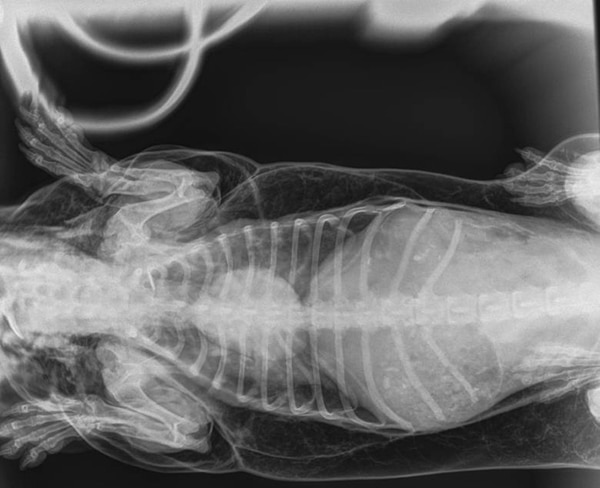

Alarmados, tomaron a Trevor y lo llevaron de urgencia a una guardia veterinaria. De inmediato le hicieron radiografías. Y allí encontraron la respuesta al misterio: tenía un orificio en su tráquea.

Entonces, cada vez que el pobre salchicha inhalaba el aire se filtraba por ese agujero y dirigiéndose no sólo a sus pulmones, sino al resto del cuerpo, atravesando sus músculos y llegando hasta su piel.